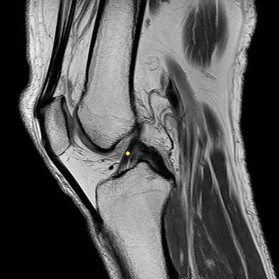

Question 2

A 28-year-old male sustains a severe hyper-dorsiflexion injury to his ankle in a motor vehicle accident, resulting in a Hawkins Type III talar neck fracture. Which of the following arteries provides the predominant blood supply to the body of the talus, placing it at significant risk for avascular necrosis in this injury?

Explanation

The artery of the tarsal canal, which is a branch of the posterior tibial artery, provides the dominant blood supply to the talar body. In a Hawkins Type III fracture (talar neck fracture with subtalar and tibiotalar dislocation), the blood supply from the artery of the tarsal canal, the artery of the sinus tarsi, and capsular vessels are disrupted, leading to an avascular necrosis (AVN) rate approaching 100%.